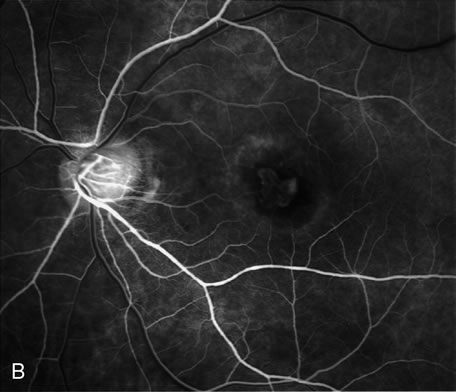

The diagnosis of CSC may be difficult if there is neither RPE detachment nor evidence of leakage into the subretinal space. Possible causes of a neurosensory elevation without evidence of leakage in the macula include CSC with the RPE detachment located outside the macular area (Fig. 28), CSC with a healed leak (in which case the neurosensory detachment should resolve soon), peripheral retinal hole, choroidal tumor, congenital optic nerve pit, and idiopathic uveal effusion syndrome. There are several other considerations in a patient who presents with a localized serous detachment of the macula, including age-related macular degeneration,162–164 a macular hole in a patient with high myopia, malignant hypertension, toxemia of pregnancy, collagen vascular disease, disseminated intravascular coagulation, choroidal inflammatory disease, Coat's disease (Fig. 29), and ocular contusion. Usually, these conditions are diagnosed based on clinical examination. ICG angiography may be helpful in differentiating CSC from AMD. On ICG studies there is often diffuse choroidal hyperpermeability in patients with CSC.165–181

Fig. 28. A 30-year-old woman had loss of vision in the right eye to 20/80. The patient was on systemic corticosteroid treatment for renal transplant rejection. A. Clinical photograph of the right eye demonstrates a neurosensory macular detachment. B. Late-phase fluorescein angiography reveals the presence of three3 actively leaking PEDs above the optic disc. Note the similarity between this case and the case illustrated in Figure 27 with PCV.